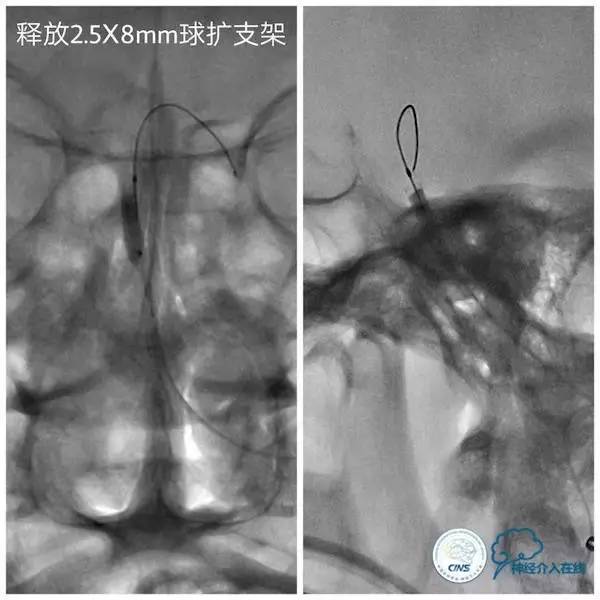

扩张后沿微导丝送入Apollo支架(2.5mm×8mm),释放支架后造影显示支架贴壁良好,狭窄明显改善,前向血流TICI3级(图9,10)。

图9

图10

1.治疗基底动脉狭窄时,如果双侧大脑后动脉P1段发育不良或缺如,选择粗大的小脑上动脉作为微导丝的着陆区还是可行的,但要避免输送系统时导丝前窜穿孔危险。

2. 本例狭窄程度重且病变短,治疗过程中担心病变过硬导致直接放置球囊扩张支架移位,故选择预先球囊扩张。